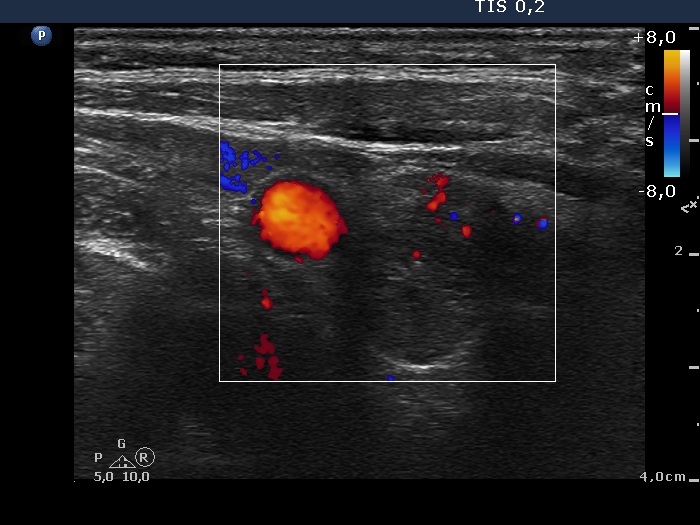

Chronic lymphocytic thyroiditis - Case 86. (ultrasonographic picture 6)

Lower part of the right lobe, horizontal scan, color Doppler mode. There are signs of intralesional blood flow.